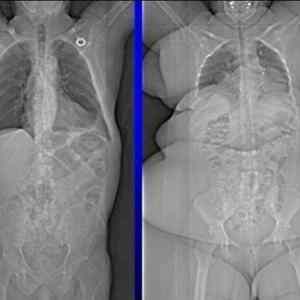

@llu: Ač to tak nevypadá, tak ta tlustá paní je celkově o kus menší - srovnej si vzdálenosti od krku k pánvi.

Zaujalo ma, že tá tlstá pani má akési "stlačené" pľúca. V porovnaní so štíhlou osobou ich má oveľa menšie, hoci zrejme ich potrebuje pri svojej váhe oveľa viac (taký človek sa predsa často zadýchava atď).